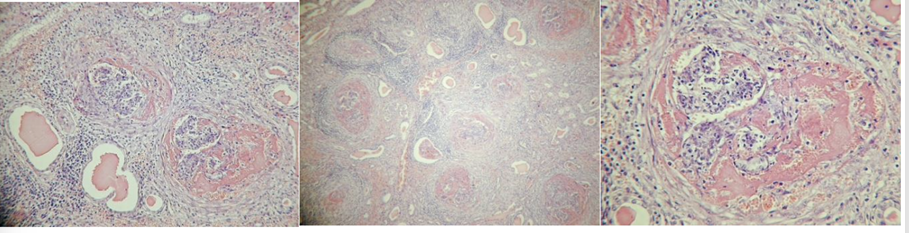

Glomerulonephritis chronica

Bilde 1: hyaline in glomeruli and tubules

bilde 2: periglomerulitis chronica, gradual fibrotization of glomeruli

bilde 3: higher magn. of bilde 1, glomeruli with neutrophils and hyaline